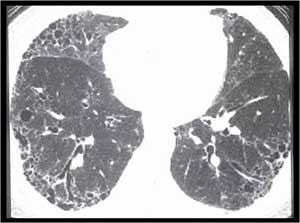

风湿性疾病肺受累常见影像学表现

非特异性

普通

急性间质性

淋巴细胞间质性

脱屑性

COP

类风湿结节